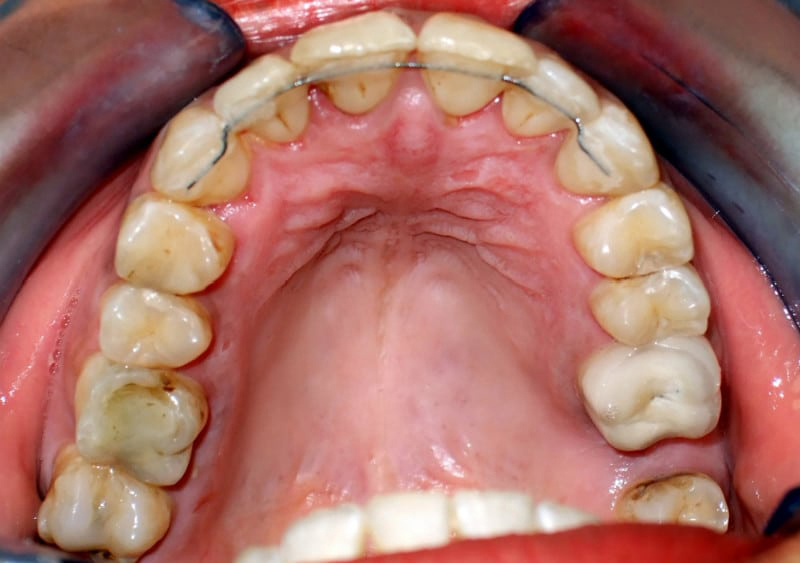

Ένα αρκετά απαιτητικό περιστατικό με έντονο προγναθισμό της κάτω γνάθου, σταυροειδή σύγκλειση στην πρόσθια περιοχή, και αρκετά χαλασμένα δόντια. Αφού έγινε εξαγωγή των τερηδονισμένων δοντιών, τοποθετήθηκαν αισθητικοί ακίνητοι μηχανισμοί για δύο χρόνια. Το αποτέλεσμα παραμένει αναλλοίωτο για πάνω από τρία χρόνια, με τη χρήση κινητών και σταθερών συγκρατητικών μηχανισμών. Στα κενά που παρέμειναν τοποθετήθηκαν εμφυτεύματα.